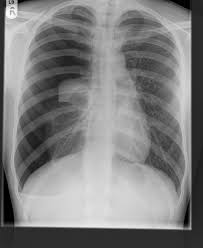

This is termed spontaneous pneumothorax. Pneumothoraces can be even further classified as simple, tension, or open. Pneumothorax nursing interventions, treatment, pathophysiology nclex review for the different types of pneumothorax: Pneumothorax, also called a collapsed lung, is when air gets between one of your lungs and the wall of your chest. It is reasonably common and has many different causes.

Other signals that the problem may be a collapsed lung are: Normally, the outer surface of the lung sits next to the inner surface of the chest wall. The lung and the chest wall are covered by thin membranes called pleura. It occurs when air accumulates between the parietal and visceral pleura inside the chest. Pneumothoraces can be even further classified as simple, tension, or open. A pneumothorax is an abnormal collection of air in the pleural space between the lung and the chest wall. Pneumothorax is defined as the presence of air or gas in the pleural cavity (ie, the potential space between the visceral and parietal pleura of the lung), which can impair oxygenation and/or. A pneumothorax occurs when air leaks into the space between your lung and chest wall. The pressure causes the lung to give way, at least partly. Pneumothorax is classified as spontaneous or traumatic. Hemothorax occurs when there is blood in that. This air pushes on the lung, which makes it collapse. The air accumulation can apply pressure on the lung and make it collapse.

In a healthy body, the lungs are touching the walls of the chest. A pneumothorax is a collection of air outside the lung but within the pleural cavity. It is reasonably common and has many different causes. Open pneumothorax vs closed pneumothorax. Pneumothorax, also called a collapsed lung, is when air gets between one of your lungs and the wall of your chest.

While secondary pneumothorax is caused by an underlying pulmonary disease, the spontaneous type occurs in healthy individuals without obvious cause. When there is no apparent cause, the condition is known as spontaneous pneumothorax. Other signals that the problem may be a collapsed lung are: Pneumothorax is classified as spontaneous or traumatic. Normally, the outer surface of the lung sits next to the inner surface of the chest wall. There are several variations of pneumothorax. It occurs when air accumulates between the parietal and visceral pleura inside the chest. A tension pneumothorax can cause complete collapse of the nearby lung and can push the heart and major blood vessels to the other side of the chest. A collapsed lung requires immediate medical care. Patients with a pneumothorax typically report dyspnoea and chest pain. This air pushes on the outside of your lung and makes it collapse. The lung and the chest wall are covered by thin membranes called pleura. Also known as pneumothorax, collapsed lung is a rare condition that may cause chest pain and make it hard to breathe.

Patients with a pneumothorax typically report dyspnoea and chest pain. Pneumothoraces can be even further classified as simple, tension, or open. Pneumothorax is defined as the presence of air or gas in the pleural cavity (ie, the potential space between the visceral and parietal pleura of the lung), which can impair oxygenation and/or. In a healthy body, the lungs are touching the walls of the chest. The definition of a pneumothorax is an accumulation of air outside the lungs, but inside the chest wall. It is reasonably common and has many different causes. A pneumothorax is a collection of air outside the lung but within the pleural cavity. A pneumothorax can be a complete lung collapse or a collapse of only a portion of the lung. A pneumothorax occurs when air leaks into the space between the lung and chest wall (called the pleural space). This air pushes on the lung, which makes it collapse. Also known as pneumothorax, collapsed lung is a rare condition that may cause chest pain and make it hard to breathe. A large pneumothorax can squash the lung and cause it to collapse. This is termed spontaneous pneumothorax.